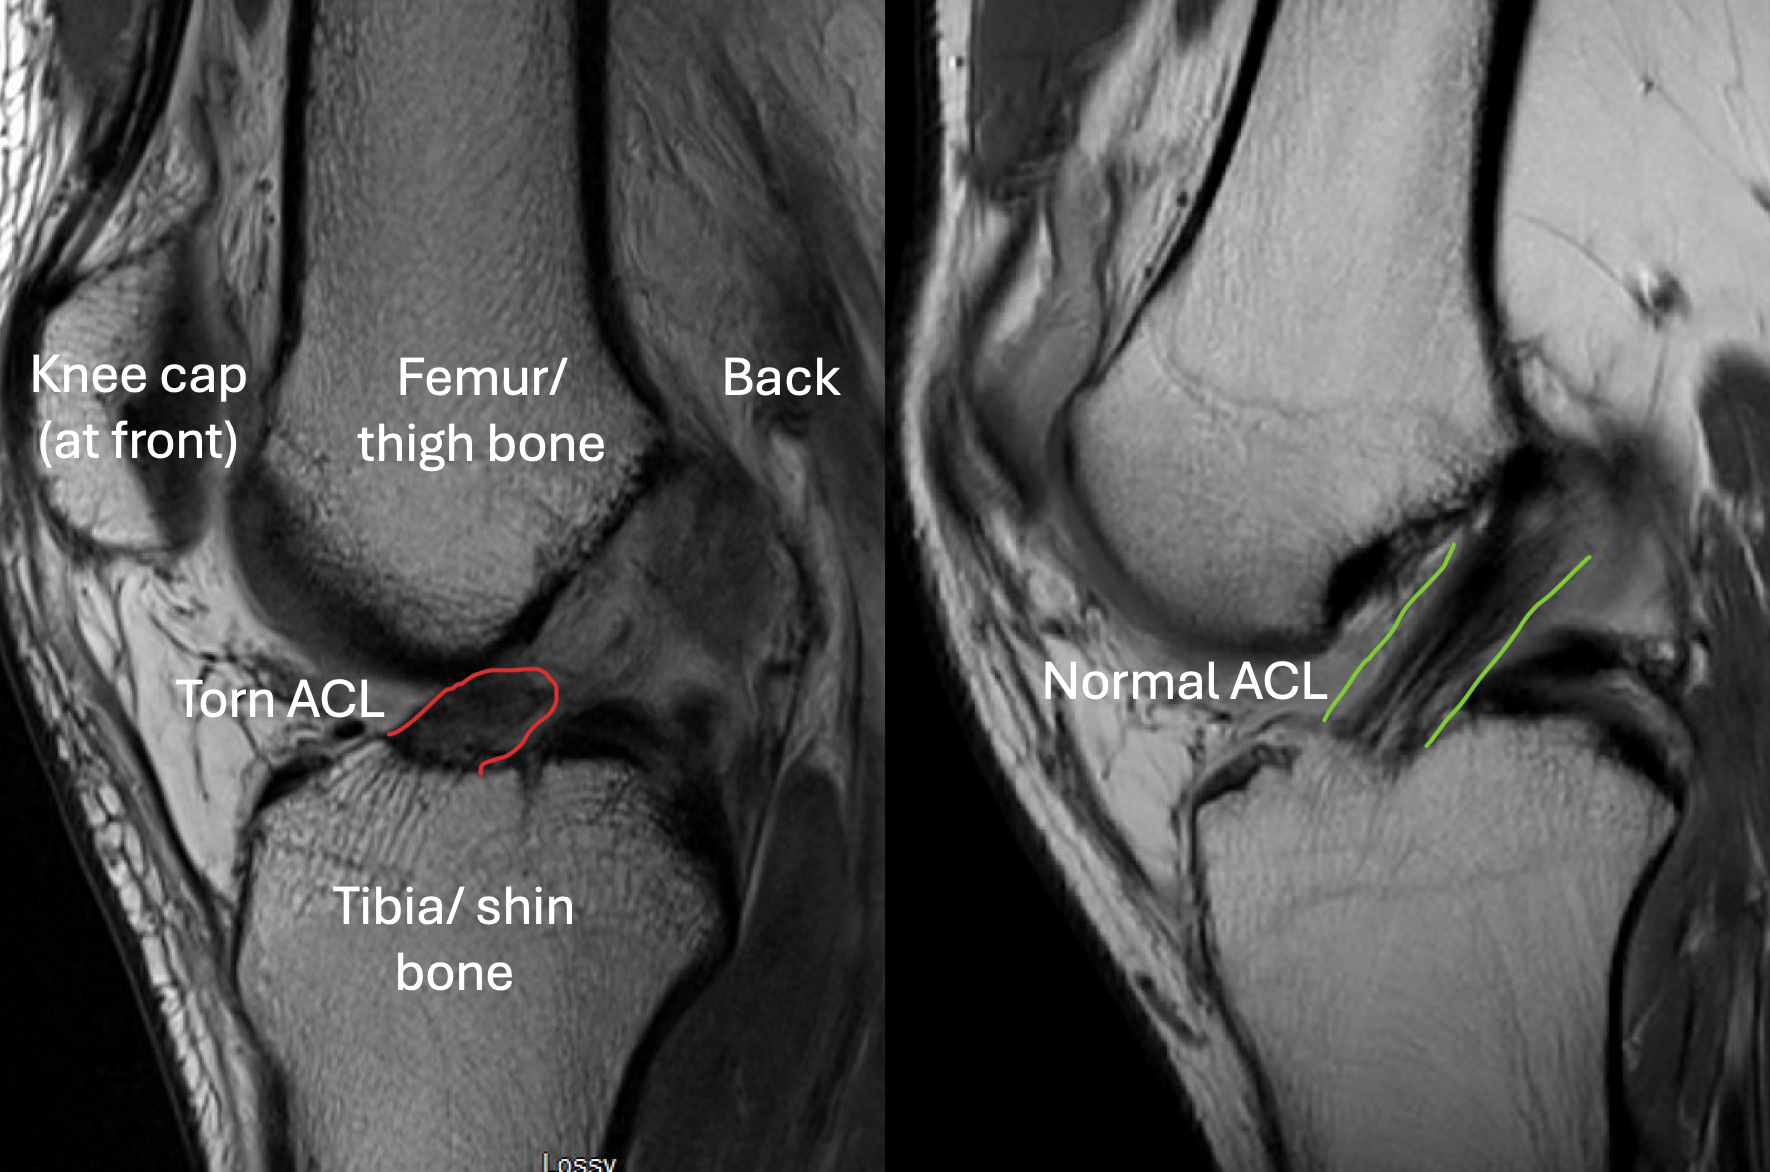

MRI Imaging

MRI confirms:

ACL tear on MRI

• ACL rupture

• Meniscal tears

• Cartilage injury

• Bone bruising

• High-quality imaging is essential. To book an MRI click here

Delayed imaging risks missing meniscal tears.